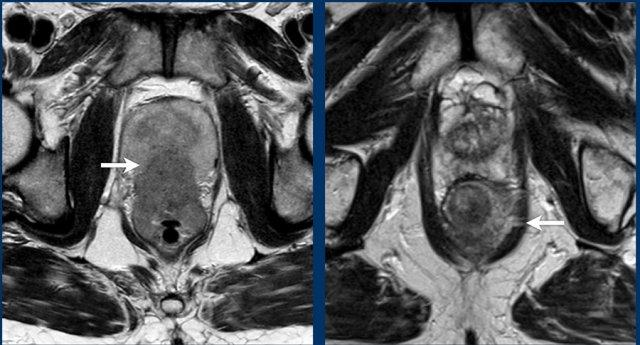

Cạm bẫy: Tránh đánh giá quá mức xâm lấn phúc mạc trong các khối u trực tràng cao

Điểm Chính:

Trong các khối u trực tràng đoạn gần, trực tràng và phúc mạc thường nằm rất gần nhau về mặt giải phẫu.

Điều này đơn thuần không cho thấy bệnh T4a.

Tiêu Chí Chẩn Đoán cho cT4a:

- Tín hiệu khối u thực sự lan rộng vào hoặc vượt qua phúc mạc/nếp gấp phúc mạc

- Dày màng bụng do khối u gây ra

Ví dụ hình ảnh:

- Trái:Khối u nằm gần phúc mạc và bàng quang (mũi tên trắng), nhưng không xâm lấn ra ngoài lớp cơ thành ruột hoặc vào phúc mạc—không phải T4a.

- Phải:Tín hiệu khối u lan vào phúc mạc (mũi tên vàng)—xác nhận xâm lấn T4a.